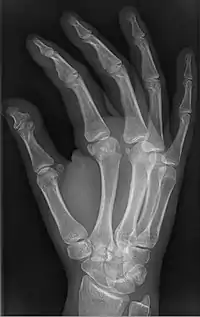

| Brachyphalangy of the thumb's distal phalanx, also known as brachydactyly type D, with otherwise normal phalanges of the 2nd-5th digits | |

Brachyphalangy is a condition in which one or more of the phalanges of the fingers and toes are smaller than normal.[1]

This condition is caused by either fusion or early closure of the phalange's growth plate. One example is brachydactyly type D, which is caused by an early closure of the thumb's distal phalange, leading to a congenitally short thumb with a similarly short and wide thumb nail.